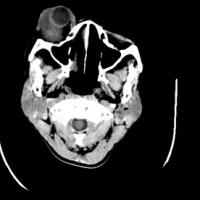

*Case 5 : Dr Garba Dahiru Waziri

email: wazirdg@gmail.com

Clinical detail: A 45-year-old female patient who presented to our hospital with history of progressive proptosis of the right eye of 8 years duration and progressive loss of vision of 3 years duration. There was associated history of periorbital pain and discomfort as the proptosis progressed. She gave no medical history of trauma, instrumentation or blunt injury to the face. There were no other contributory complaints.

Please, consult the images and virtual slides of Case 5 below.